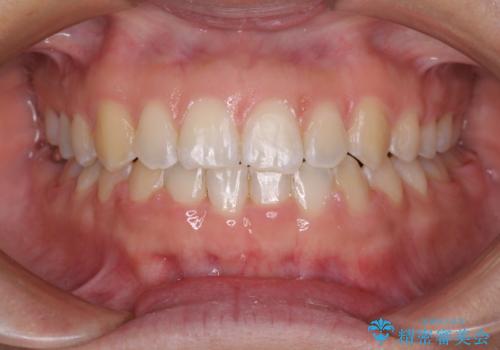

下の前歯が上の前歯を突き上げるように咬合するため、咬み合わせの位置を改善しながら隙間を閉じていきました。

元々の歯並びが悪くなかったため、9ヶ月で綺麗に仕上がりました。

すきっ歯は後戻りを起こしやすいため、上下ともに歯の裏側を細いワイヤーで固定した上で、リテーナーのマウスピースを装着していただいています。